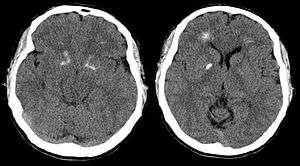

Brain computer tomography cuts of the person, demonstrating basal ganglia and periventricular calcification.[6]